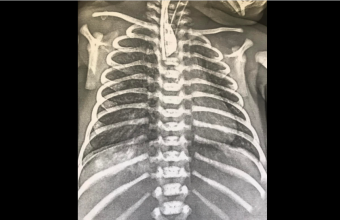

Новонароджений Данилко народився із порушеним ковтанням. Після проведених обстежень у нього діагностували одну із найважчих вад розвитку – атрезія стравоходу. Хлопчик уже переніс кілька операцій, проте у майбутньому на нього чекає його головне оперативне втручання.

«Надалі ми плануємо радикальну корекцію вродженої вади у дитини – формування «штучного стравоходу», що передбачає переміщення частини кишківника з черевної порожнини у грудну клітку. Таким чином ми відновимо частину відсутнього стравоходу у дитини», - додав лікар.